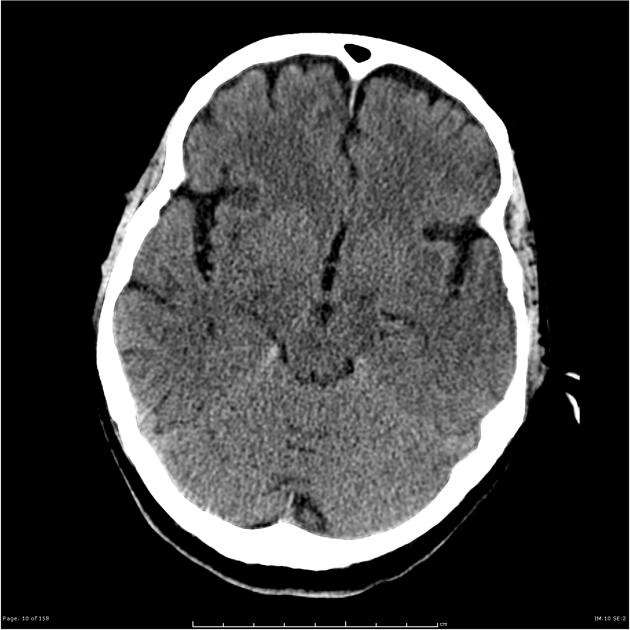

Phù não (Cerebral Edema)

Phù độc tế bào (Cytotoxic Cerebral Edema)

Phù não hỗn hợp (Combined Cerebral Edema)